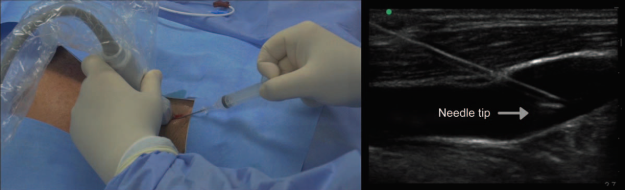

An illustrative academic video of the techniques was prepared to provide a graphic description of US-guided in plane and oblique longitudinal internal jugular access and US-guided in-plane longitudinal subclavian vascular access (Fig. 3) (Watch the video here: http://links.lww.com/RCA/A57).

Transverse and/or longitudinal planes can be used for localization of the selected vein and catheter placement. 16 The transverse position (short axis) is useful for accessing vessels near the skin surface such as the internal jugular vein. 17,18 For deeper vessels, as is the case with the common femoral vein, a combined approach may be used, starting with the transverse position to identify the vessel, followed by rotation to the longitudinal view, initial needle advancement, and cannulation completion. 19